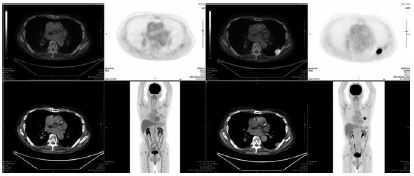

核医学ビューでさくさく比較

PETの読影は少し特殊である。これまではWorkstationでCT画像、PET元画像、Fusion画像、全身MIP画像を設定して、並べて表示する事が多かった。これが数回のクリックでViewer上に別のシートとして表示される。さらに特筆は過去画像との比較が容易にできる事である。図1は左側が今回、右側が過去画像の表示で、もちろん全ての画像が同期している。このビューを出すのに10秒かからないのだから、さくさく比較読影が可能となった。癌の治療効果判定などPETは比較読影する事が多く、画像シリーズを並べるだけで大変だったのが、大きな時間短縮につながった。さらにタグのクリック一つで全ての画像をSagittal像、Coronal像に変換できるのも便利である。VOI(volume of interest)でのSUV(standardized uptake value)測定はワンキーで可能であり、過去画像とのSUV値の変化をみるのがこれまで大変だったが、かなり簡単にできるようになった。さらに設定でMTV(代謝腫瘍体積)、TLG(総腫瘍代謝量)の測定値の表示が可能であり、基本的に研究ベースで使っていた値が、臨床に直結できるようになった。これらのViewerの進歩が、研究と臨床の間をつなぐ柱の一つになっていくのだろう。